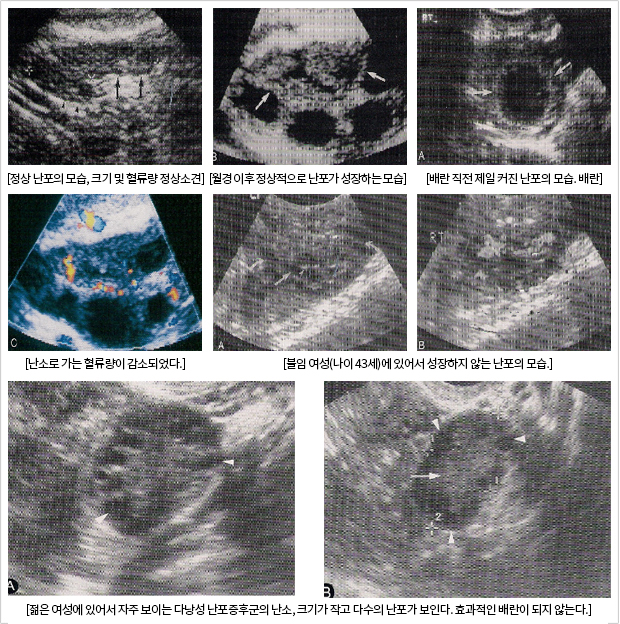

³­¼Ò Æò°¡

¿ù°æ½ÃÀÛ°ú µ¿½Ã¿¡ Àڱ󻸷ÀÌ ´Ù½Ã ÀÚ¶ó°í ³­¼ÒÀÇ ³­Æ÷µµ ¼ºÀåÀ» ½ÃÀÛÇÏ°Ô µÇ¾î ¹è¶õ Àü Åë»ó °¢°¢ÀÇ ³­¼Ò¿¡¼­ 2-3°³ÀÇ Á¤»ó³­Æ÷°¡ °üÂûµÈ´Ù. ¹è¶õ Àü ³­Æ÷´Â Åë»ó 1.8cm ÀÌ»ó µÇ¾î¾ß Á¤»óÀûÀÎ ¹è¶õ°ú ³­ÀÚ¸¦ ¹èÃâ ÇÒ ¼ö ÀÖÀ¸¸ç Àß ÀÚ¶óÁö ¾ÊÀº ³­Æ÷´Â ¹è¶õÀ» ÇÒ ¼ö°¡ ¾ø´Ù. ´Ù³¶¼º ³­Æ÷¸¦ º¸ÀÌ´Â ¿©¼º¿¡ À־´Â ¿ù°æÁ÷ÈĺÎÅÍ ´Ù¼öÀÇ ³­Æ÷°¡ °üÂûµÇÁö¸¸ È£¸£¸ó ÀÌ»óÀ¸·Î ³­Æ÷°¡ Àß ¼ºÀåÇÏÁö ¾Ê¾Æ ¹è¶õ Á÷Àü¿¡ Ư¡ÀûÀ¸·Î 1cm ÀÌÇÏÀÇ ´Ù¼öÀÇ ³­Æ÷°¡ º¸ÀÌ¸ç ³­ÀÚ ¹èÃâÀ» ¾î·Æ°Ô ¸¸µç´Ù. ³­¼ÒÀÇ ±â´ÉÀº ƯÈ÷ ³ªÀÌ¿Í °ü·ÃÀÌ ¸¹À¸¸ç È£¸£¸ó ºÐºñ°¡ °¨¼ÒÇÔÀ¸·Î½á ³­Æ÷ÀÇ ¼ºÀåÀÌ ¾ïÁ¦µÇ¾î ¹è¶õ±â°¡ °¡±î¿öµµ ³­Æ÷°¡ Àß º¸ÀÌÁö ¾ÊÀ¸¸ç ³­¼Ò·Î °¡´Â Ç÷·ù°Ë»ç¿¡¼­µµ Ç÷·ù·®ÀÇ ±Þ°ÝÇÑ °¨¼Ò¸¦ º¼ ¼ö ÀÖ´Ù

ÀÓ½ÅÀº Àß ¾Æ½Ã´Ù½ÃÇÇ ¿ù°æ Áֱ⿡ µû¸¥ È£¸£¸ó¿¡ ÀÇÇÑ Á¤»óÀûÀÎ Àڱ󻸷°ú ³­¼ÒÀÇ ¼ºÀåÀÌ Á¶È­·Î¿ö¾ß ÇÏ¸ç ¹è¶õ½Ã±â¿¡ ÀûÀýÇÑ ³­ÀÚ¹èÃâÀÌ µÇ¾î¾ß ¿©¼ºÃøÀÇ Áغñ°¡ ³¡³ª´Â °ÍÀÌ´Ù. °ñ¹Ý³»¿¡ ÀÖ´Â Àڱðú ³­¼ÒÀÇ º¯È­¸¦ Á¤È®È÷ ¾Ë±â À§Çؼ­ ÃÊÀ½ÆÄ °Ë»çÀÇ Çʿ伺ÀÌ ´ëµÎµÈ´Ù.